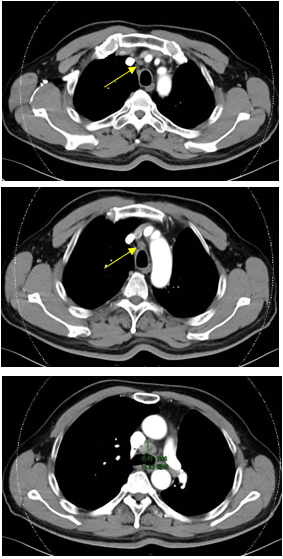

PET-CT(2023年9月):右下肺叶发现6.9×6.7×6.6cm的FDG高摄取肿块,伴右侧第7、8肋骨侵犯可疑,右肺门淋巴结肿大,双肺上叶多发结节,考虑腺癌谱系疾病。

CT及PET-CT随访(2023年11月、2024年1月):评估新辅助治疗效果,右下肺叶肿块缩小,右肺门淋巴结代谢活性消失,右肺上叶结节稳定但代谢活性降低,左肺上叶及双侧磨玻璃样病变稳定。

新辅助治疗:患者接受4周期新辅助化疗联合免疫治疗(培美曲塞、顺铂、纳武利尤单抗),治疗后影像学显示肿块缩小,代谢活性降低。

手术治疗:2024年1月行右肺下叶切除术及右肺上叶楔形切除术,术中病理显示右肺下叶为腺癌伴SCLC灶,右肺上叶为腺癌。术后病理分期:右肺下叶腺癌为ypT2aN0M0(IB期),伴SCLC灶,考虑为治疗后转化;右肺上叶腺癌为ypT1bN0M0(IA2期)。